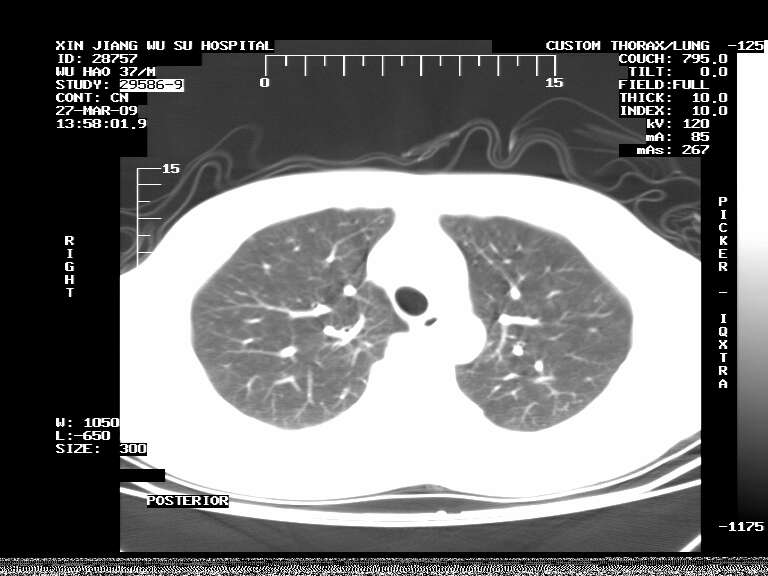

男,37岁,体检胸透发现阴影。

患者体检发现 无症状 左肺下叶占位,边缘模糊,可见血管聚束、分叶、胸膜牵拉,增强呈不均匀性强化。 首先考虑左肺下叶周围型肺癌,建议穿刺活检。

左肺下叶见一结节病变,边缘欠清不光滑,与胸膜粘连且胸膜局限性增厚,注药后呈环形强化,动脉期壁呈明显点环状强化,静脉期壁强化减低,中心密度低无强化,灶周无明显的卫星灶和水肿区(晕征)---考虑周围性肺癌,不除外感染性病变,建议穿刺活检。

左肺下叶软组织病灶,密度较高,内见点状钙化,其周围见子灶,邻近胸膜扁平样增厚.c+病灶强化明显,中心强化弱.诊断:左肺下叶结核瘤.

左肺下叶大片实变影,内靠胸膜见不规则更高密度结节灶,边缘强化,相邻胸膜增厚,胸膜下脂肪线存在。考虑炎症,结核可能。